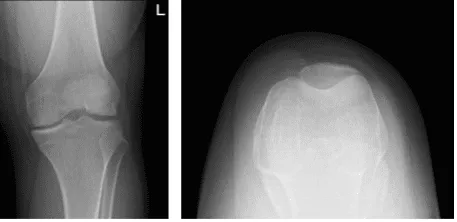

Patient is 19 year-old-male patient with pain in his left knee. It started after he slipped while playing soccer at home. His X-ray were presented and reviewed, though there are no significant degenerative and no acute fracture.

His history and examination are strongly suggestive of ACL rupture with possible lateral meniscus tear left knee. Other symptoms were not present. Further diagnostic testing is required at this time. Patient will move his knee and be WBAT with crutches.

Left knee X-ray complete with patella